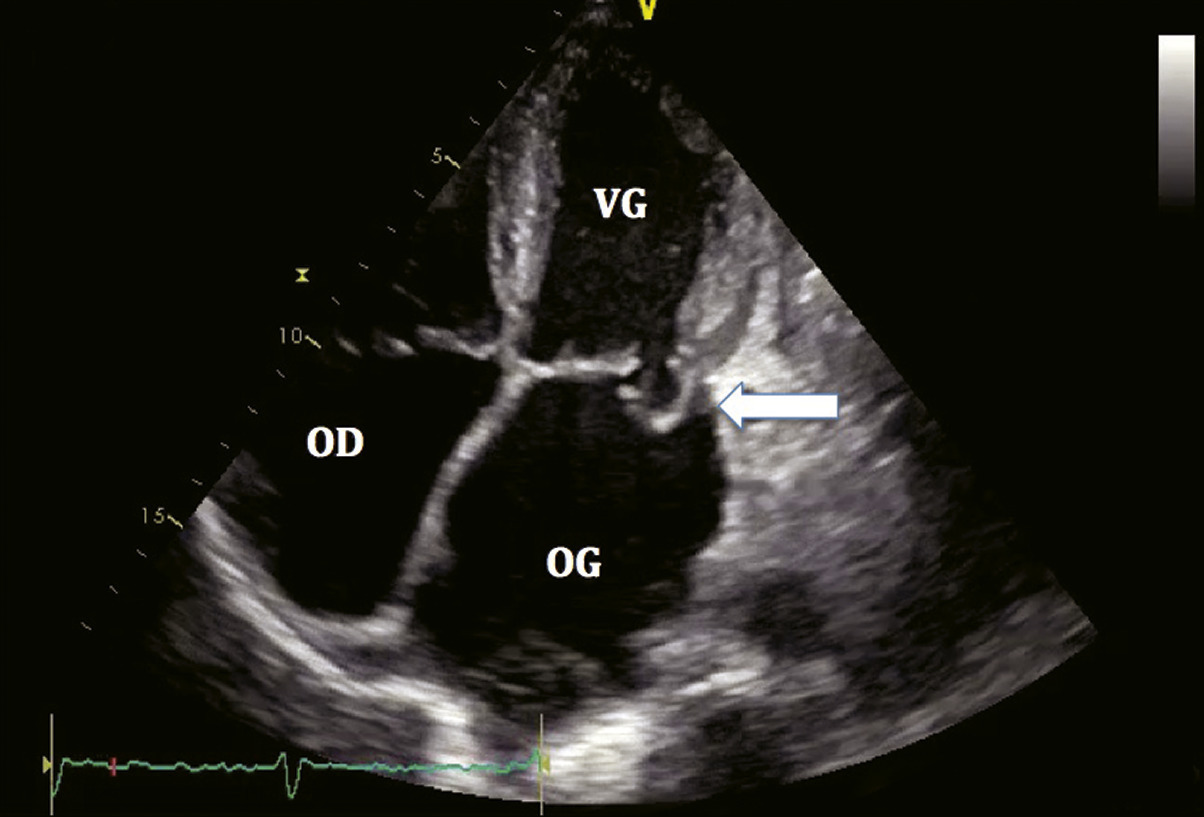

L’ETT est l’examen clé pour le diagnostic des valvulopathies (fig. 6).

Diagnostic positif : on observe le défaut de fermeture des feuillets mitraux et la régurgitation en Doppler couleur.

Diagnostic de sévérité, quantification : l’évaluation de la sévérité d’une régurgitation est fondée essentiellement sur la méthode de la zone de convergence ou PISA (proximal iso-velocity surface area), qui permet le calcul d’une surface de l’orifice régurgitant et d’un volume régurgité. Plus la SOR et le VR sont importants, plus la fuite est sévère. Une insuffisance mitrale sera considérée comme sévère si SOR ≥ 40 mm2 et/ou VR ≥ 60 mL pour une insuffisance mitrale organique ; SOR ≥ 20 mm2 et/ou VR ≥ 30 mL pour une insuffisance mitrale fonctionnelle.

Diagnostic étiologique : l’aspect de l’appareil valvulaire et sous- valvulaire ainsi que l’appréciation du mécanisme de la fuite (classification de Carpentier) permettront, avec les données cliniques, de déterminer la cause de l’insuffisance mitrale.

Évaluation du retentissement : on recherche systématiquement :

• une dilatation de l’OG ;

• une dilatation du ventricule gauche (mesure des diamètres et volumes) ;

• une altération de la FEVG ;

• une hypertension pulmonaire ;

• un retentissement sur les cavités droites.

Recherche d’une atteinte des autres valves ou de l’aorte : elle complète le bilan de toute valvulopathie.